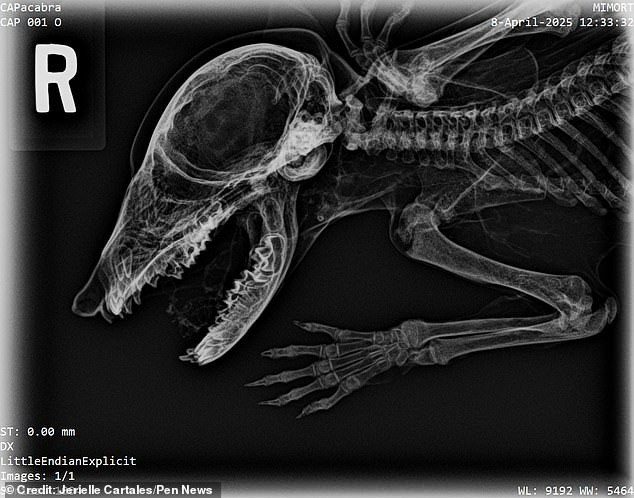

Xác ướp “Capacabra” hiện đã được chụp X-quang và so sánh bộ xương của nó với các loài khác đã biết. Theo đó, các chuyên gia loại bỏ những ứng cử viên hàng đầu như chó, mèo và chuột. Từ những đặc điểm của bộ xương, các chuyên gia suy đoán “Capacabra” có thể là một con gấu mèo. Hộp sọ và mõm của con vật này khá trùng khớp với đặc điểm của loài gấu mèo. Tuy nhiên, do xác ướp thiếu mẫu răng nên các chuyên gia chưa thể khẳng định đó có phải là một con gấu mèo hay không.